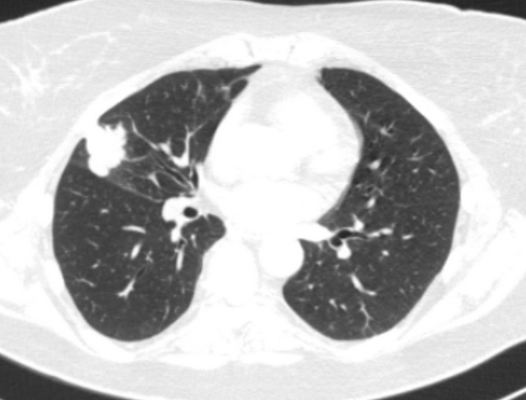

У пациента был выявлен раковый узел в 6 сегменте нижней доли слева. После резекции путем гистологического исследования верифицирован плоскоклеточный рак легкого. Томография в данном случае не дала типичную картину злокачественного новообразования.

Периферический рак легких на КТ выглядит как очаг либо узел, расположенный на периферии органа вдалеке от корня. Обычно он имеет однородную структуру, в некоторых случаях с участками некроза, обызвествлениями и кровоизлияниями в паренхиму. Края типичной раковой опухоли неровные, с множественными «спикулами» за счет лимфангиита. При расположении вблизи плевры образование деформирует ее и подтягивает к себе. Размеры его различны - от очага (3-10 мм) до узла (10-50 мм и больше).

Типичный периферический рак легкого (аденокарцинома) на МСКТ. Справа в 6 сегменте легкого выявлен плотный мягкотканный узел со спикулами, деформирующий и подтягивающий к себе междолевую плевру.